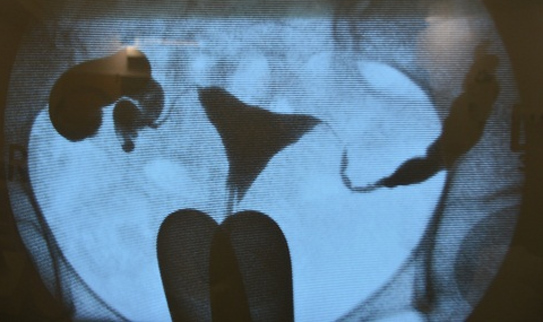

Chụp cản quang tử cung vòi trứng là phương pháp sử dụng tia – X để kiểm tra ống dẫn trứng thông suốt hay bị tắc nghẽn, đồng thời giúp quan sát hình dạng buồng tử cung có bình thường hay không. Chụp cản quang tử cung vòi trứng được thực hiện trong khoảng 30 phút và chụp vào thời điểm bệnh nhân sạch kinh nhưng trước thời điểm rụng trứng.

Bệnh nhân sẽ chụp phim ở tư thế nằm sản khoa. Bác sĩ sẽ đặt một dụng cụ là mỏ vịt vào trong âm đạo, lau sạch cổ tử cung và đặt một ống thông catheter vào lỗ cổ tử cung. Sau đó bác sĩ sẽ bơm vào buồng tử cung dung dịch có chứa chất cản quang (Iốt). Dung dịch này sẽ đi vào 2 ống dẫn trứng và vào ổ bụng (nếu ống dẫn trứng thông suốt). Những bất thường trong tử cung cũng có thể phát hiện nhờ phim X-quang.

Sau khi chụp, nếu thấy hình ảnh thuốc cản quang trong ổ bụng có nghĩa 2 vòi trứng thông tốt và kết quả được trả lời là Cotle(+) 2 bên. Sau khi chụp phim, bệnh nhân có thể sinh hoạt bình thường nhưng nên sử dụng bao cao su để tránh thai hoặc nên kiêng giao hợp một vài ngày. Lưu ý: Chụp tử cung vòi trứng không dùng để khảo sát buồng trứng hoặc chẩn đoán lạc nội mạc tử cung và không thực hiện chụp tử cung – vòi trứng khi nghi ngờ có thai.